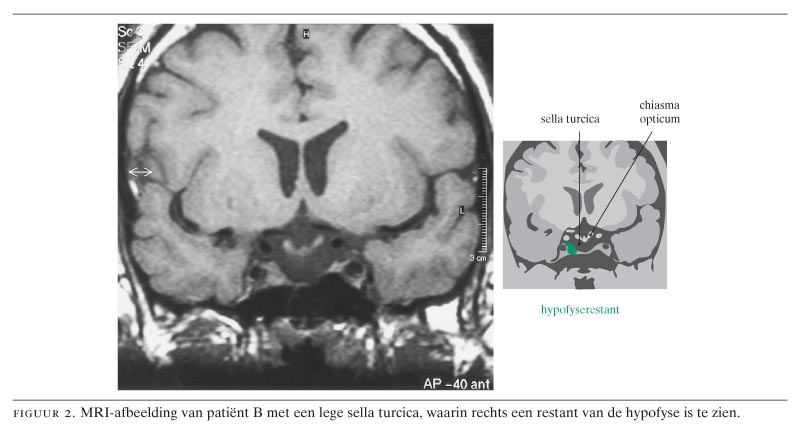

Bij 2 patiënten, mannen van 78 en 42 jaar, werd een lege sella turcica (‘empty sella syndrome’) aangetroffen. De eerste patiënt kwam met chronische vermoeidheid, bij de tweede was de lege sella ontstaan als laattijdig gevolg van een eerdere neurochirurgische ingreep, die gevolgd was door uitwendige bestraling. Beiden hadden panhypopituïtarisme. De diagnose werd gesteld met behulp van laboratoriumtests en MRI-onderzoek. Adequate behandeling bestond uit hormoonsuppletie. Het beloop van het empty-sellasyndroom is meestal goedaardig en met adequate suppletie van deficiënte hormonen wordt een goede kwaliteit van leven gehandhaafd.